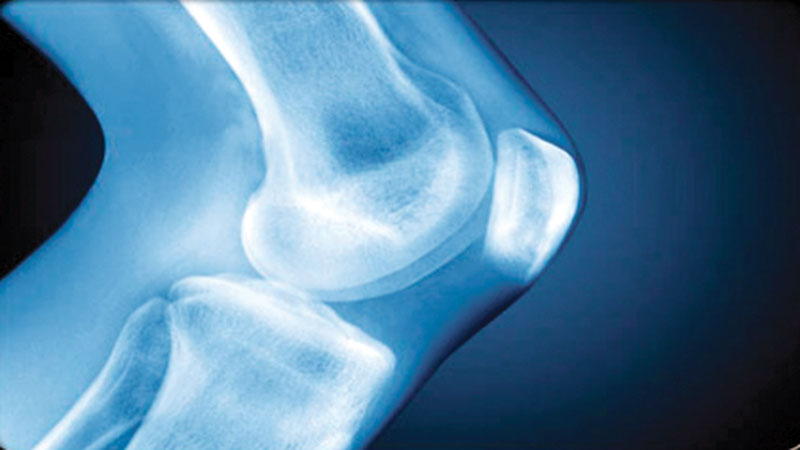

Osteoarthritis is a form of arthritis that features the breakdown and eventual loss of the cartilage of one or more joints. Cartilage is a protein substance that serves as a "cushion" between the bones of the joints. Among the over 100 different types of arthritis conditions, osteoarthritis is the most common. Osteoarthritis occurs more frequently as we age. Before age 45, osteoarthritis occurs more frequently in males. After 55 years of age, it occurs more frequently in females. In the United States, all races appear equally affected. A higher incidence of osteoarthritis exists in the Japanese population, while South-African blacks, East Indians, and Southern Chinese have lower rates.

Osteoarthritis is abbreviated as OA or referred to as degenerative arthritis or degenerative joint disease (DJD). Osteoarthritis commonly affects the hands, feet, spine, and large weight-bearing joints, such as the hips and knees. Osteoarthritis usually has no known cause and is referred to as primary osteoarthritis. When the cause of the osteoarthritis is known, the condition is referred to as secondary osteoarthritis. Primary osteoarthritis, osteoarthritis not resulting from injury or disease, is mostly a result of natural aging of the joint. With aging, the water content of the cartilage increases, and the protein makeup of cartilage degenerates. Eventually, cartilage begins to degenerate by flaking or forming tiny crevasses. In advanced osteoarthritis, there is a total loss of the cartilage cushion between the bones of the joints.